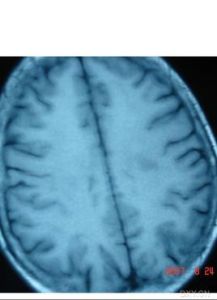

前列腺鈣化、纖維化是前列腺發生炎症癒合後留下的疤痕,是前列腺結石的前兆。由於前列腺結構特殊性,發生鈣化、結石一般沒有較好的治療方法,對於一般無症狀者也不需要進行治療。前列腺鈣化(纖維化)、結石上會滋生細菌,所以又是前列腺炎反覆發作的一個原因,所以前列腺炎和前列腺鈣化都不不容忽視。前列腺鈣化是列腺炎症愈後就留下鈣化斑,在預防和護理中需要積極防治前列腺炎等原發疾病,同時需要給予前列腺鈣化和前列腺纖維化有效的康復護理: